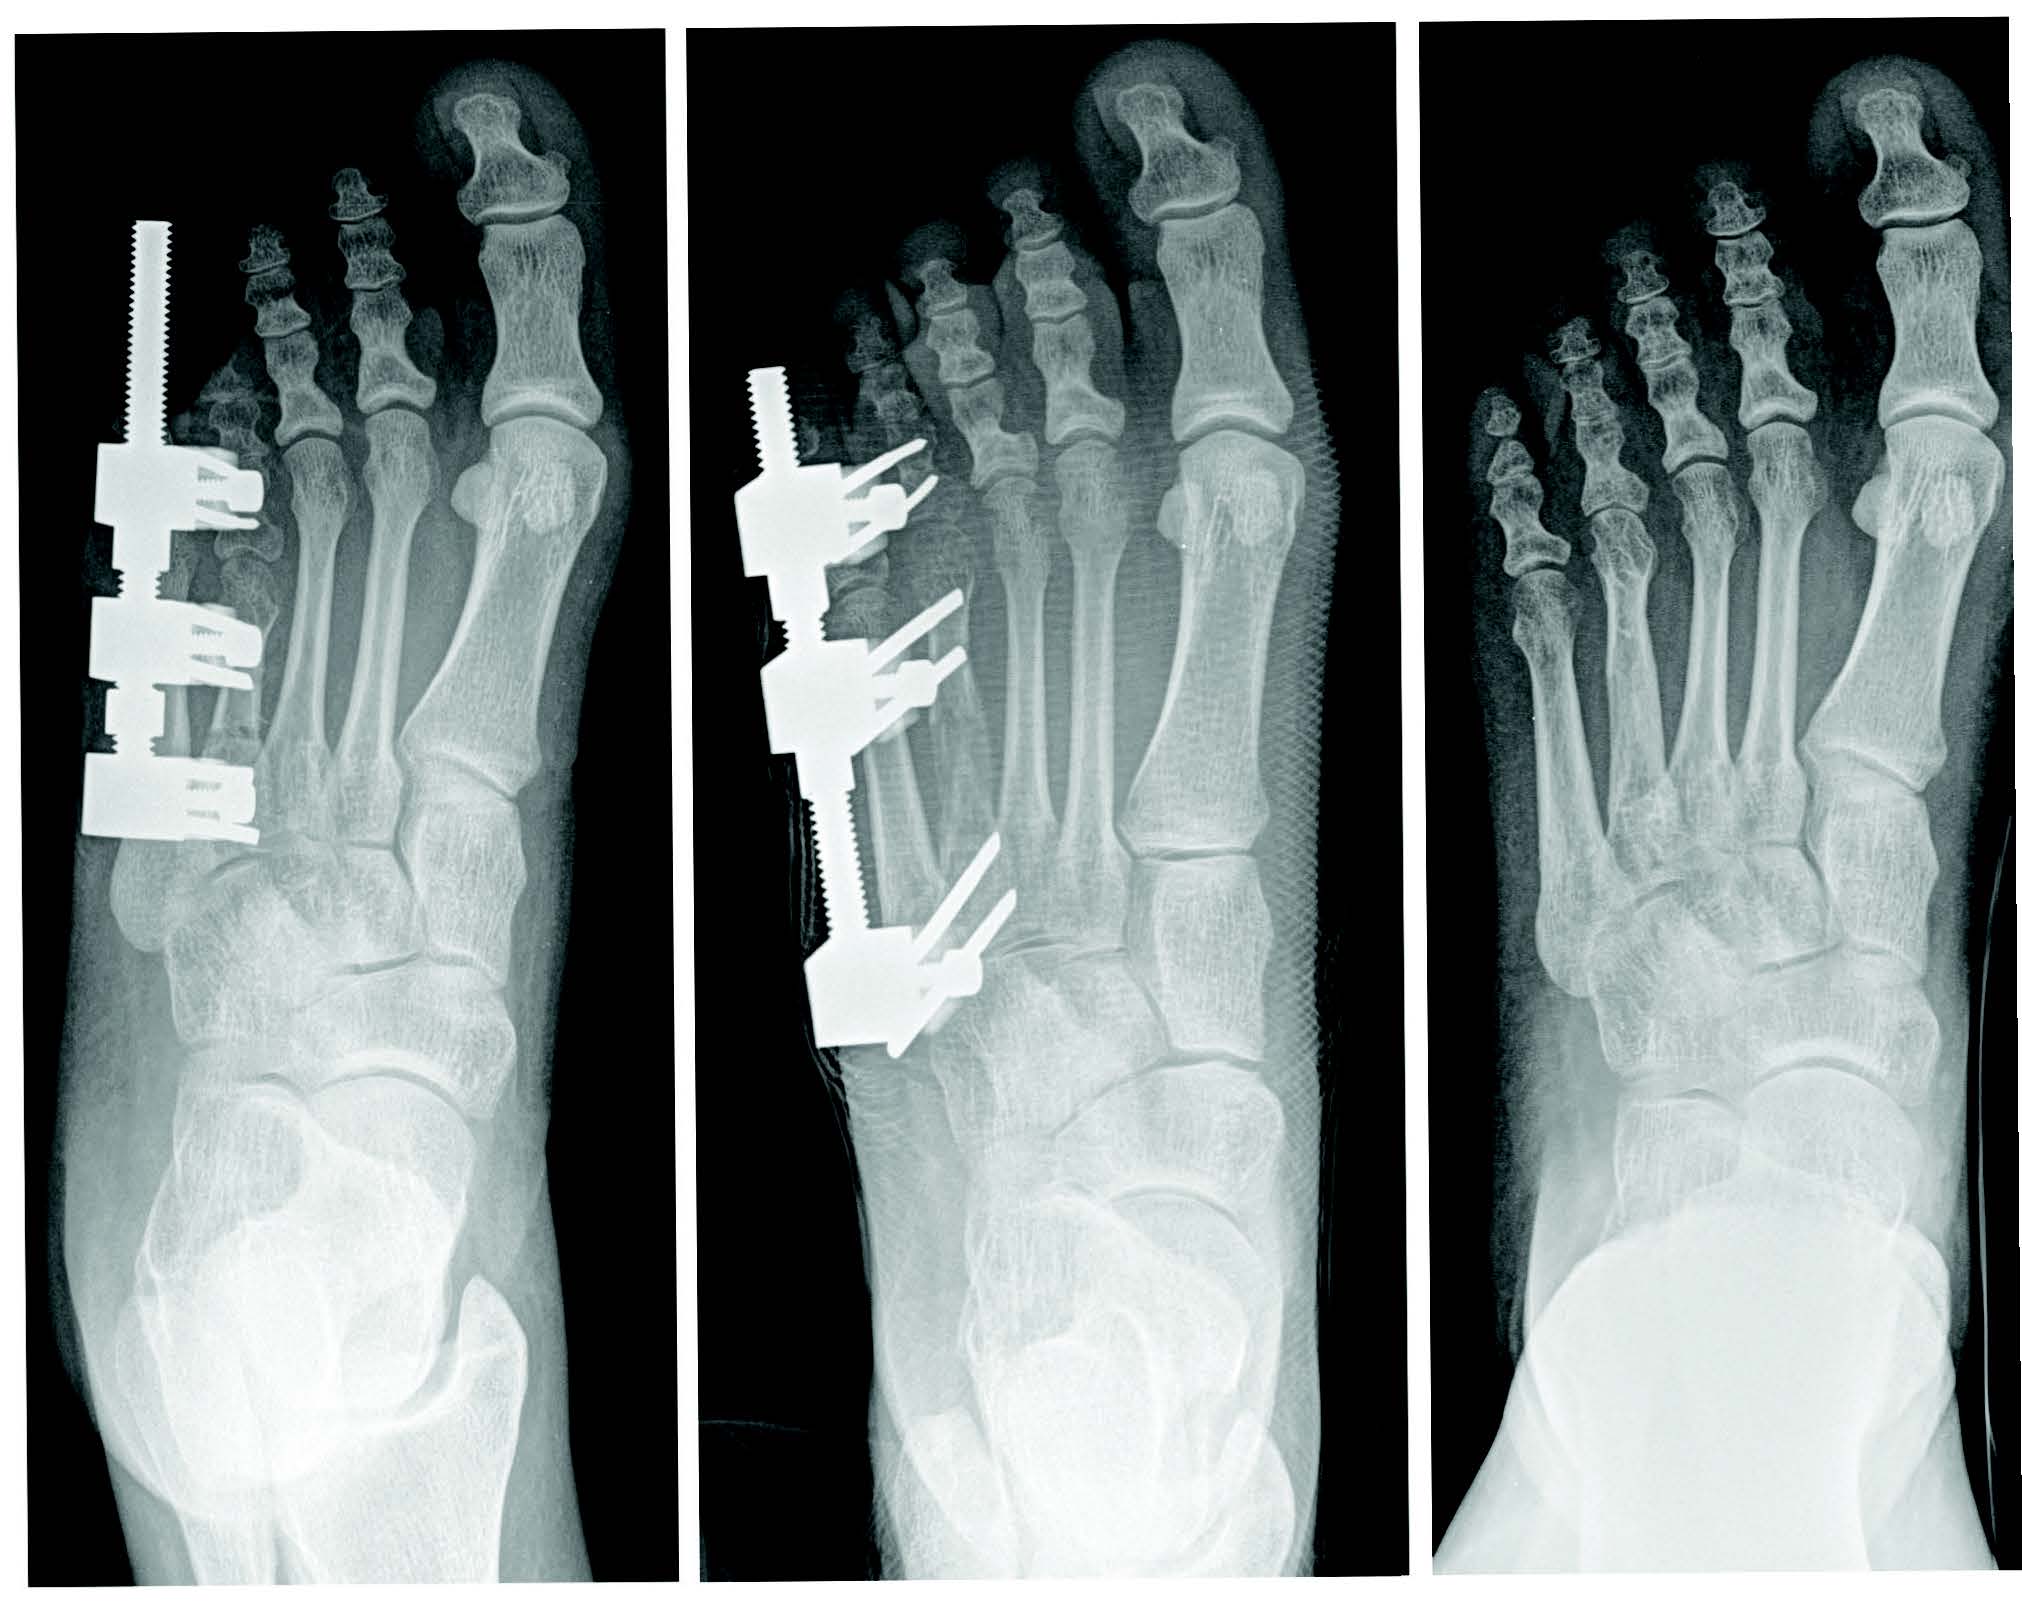

Tricortical radiographic consolidation on two orthogonal radiographs mark achievement of bony consolidation. Computed tomography may be necessary to confirm complete osseous healing in foot and ankle cases. Obtaining this endpoint then allows for removal of the external fixation.

Rate and rhythm in distraction osteogenesis significantly impacts the expression of factors involved.18 Further, several experimental studies show improved bone regeneration with continuous versus intermittent distraction osteogenesis.21 One begins distraction at a specific rate and rhythm, typically 1.0 mm a day, divided into four increments. Although this is the classically cited rate, in clinical practice, the rate can vary (0.5 mm/day to 1 mm/day in the foot and ankle) based on multiple factors including: patient age, health, medications, location and type of osteotomy.

Numerous parameters can quantify bone formation quality and speed, with the healing index (HI) being the most widely used. This is the time needed for consolidation to occur per cm of the distracted osteotomy site. Consolidation time (CT) is the time between the end of distraction and complete consolidation or hardware removal. Consolidation time is about twice as long as the distraction time in children, but may be 3 to 4 times longer in adults.16 Thus, it usually amounts to 1 month/cm in children and 2 to 3 months/cm in adults.17

Other reported complications include joint stiffness and subluxation, as well as osseous malalignment. During lengthening, there is a tendency for the bone segment in question to gradually veer off its intended course due to muscle forces or instability secondary to an inadequate external fixator construct.2,9,10 Other complications relate to the consolidation rate at the distraction site. Premature consolidation occurs as a direct result of an excessive latency period in which significant callus healing blocks the distraction. In contrast, prolonged or delayed consolidation can occur secondary to patient metabolic, environmental, or technical factors including: poor osteotomy technique, initial diastasis, or rapid distraction.9,10 Pin site tract infections, fracture after external fixator removal, and chronic regional pain syndrome have also been reported.19